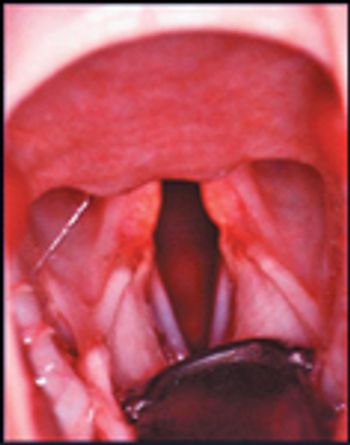

Laryngeal paralysis is recognized because of the loss of function in the paired cricoarytenoideus dorsalis (CAD) muscles, which are the only abductors of the aytenoid cartilages.